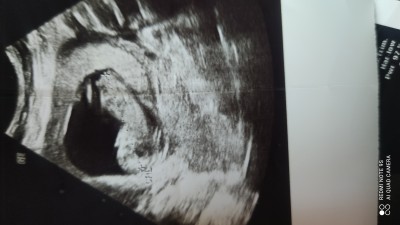

Sizce cinsiyet ne arkadaşlar

sizce içinize ne doğdu

13+5